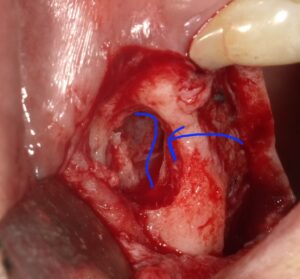

このシュナイダー膜を骨から剥がしていきます。

破らないように慎重にです。

剥がして持ち上げたスペースに人工骨を填入します。

当院の場合はここに採血させていただいた血液から

多血小板血漿の塊を作成し保護剤として貼り付けます。

青線の中がそれになります。